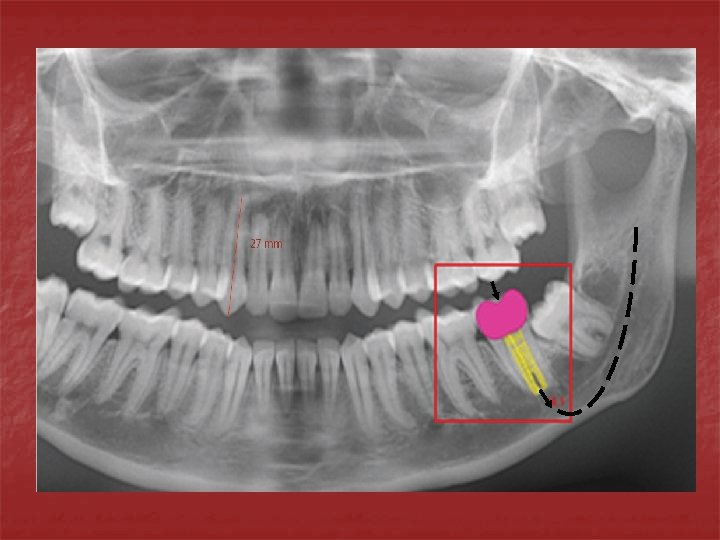

n n n Clase I: Si la pared pulpar es cóncava buscar puntos de apoyo en la periferia dela parte cóncava(tres puntos al menos) Espesor adecuado para evitar flexión del piso o fractura del material. Clase II: Anclar la restauración a nivela de la pared gingival mediante la preparación de surcos o perforaciones o inclinando la ared en sentido apico-axial.

n n n En oclusal aumentar la profundidad de la preparación porque la resistencia por flexión de una viga aumenta con el cuadrado de la profundidad. A mayor tamaño de la cavidad utilizar materiales resistentes. En esmalte: Mantener apoyo dentinario, seguir la dirección general de los prismas, no cortar prismas sin soporte en su parte interna.

Al preparar las cavidades debemos tener presente que: A mayor tejido dentario remanente mayor será la resistencia de las paredes. A mayor profundidad mayor posibilidad de fractura de las paredes. A mayor anchura mayor posibilidad de fractura de las paredes. A mayor retención adicional mayor posibilidad de fractura del las paredes. A mayor inclinación de las cúspides mayores serán las cargas a soportar y mayor será la posibilidad de fractura.